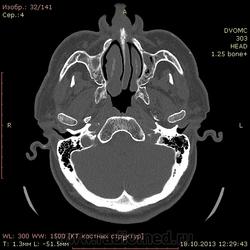

72 года. Жалобы на частые головные боли. В мозгах вроде ничего особенного, а вот пазухи...лобной нет, клиновидная недоразвитая. Вопрос вот какой:

Можно ли считать картину в, опять таки недоразвитых, верхнечелюстных пазухах (особенно слева) как хронический гайморит?(или острый такой бывает?) вся эта неоднородность и полости воздушные и мягкотканная плотность....

Написал бы как дополнение: двусторонее нарушение пневматизации в обеих в/ч, справа тотальное, слева субтотальное вспененными плотностями. Синусит? в правой в/ч возможно, полипозный (или кистознополипозный, как вам больше нравится). Рек. конс. ЛОР.